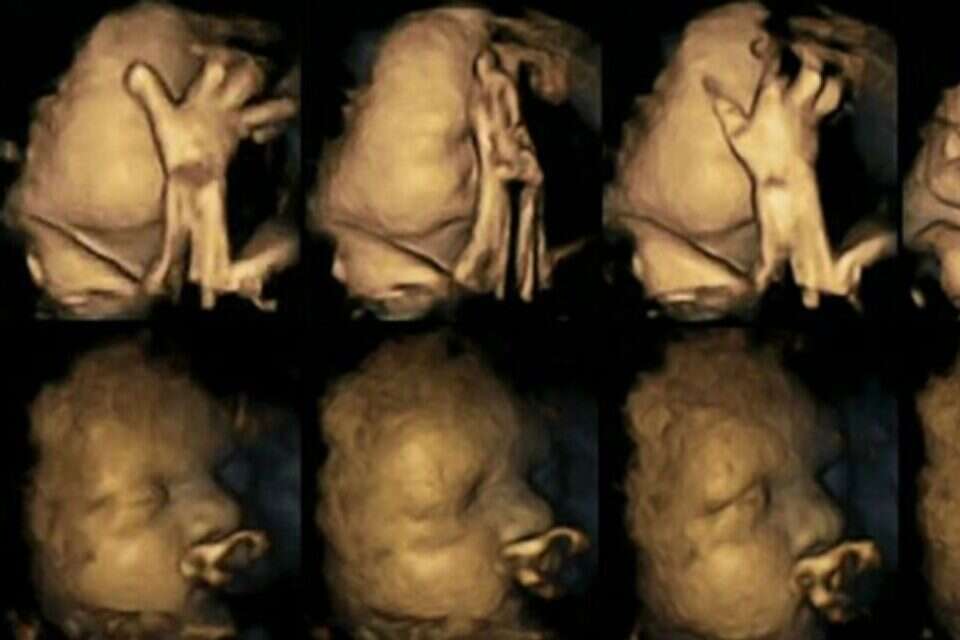

כך זה נראה במחקר של ד"ר רייסלנד. למעלה עוברים לנשים מעשנות, למטה עוברים לאימהות לא מעשנות // כך זה נראה במחקר של ד"ר רייסלנד. למעלה עוברים לנשים מעשנות, למטה עוברים לאימהות לא מעשנות

ד"ר נדיה רייסלנד עשתה שימוש בטכנולוגיה מתקדמת על מנת לנהל רישומים של מאות תזוזות של עוברים ברחם. היא עקבה אחר 20 אימהות בבית חולים במידלסבורו, אנגליה. ארבע מהאימהות עישנו מספר ממוצע של 14 סיגריות ביום. לאחר שבחנה את סריקות התמונות שיצאו בשלבי ה-24, 28, 32 ו-36 שבועות להריון, היא גלתה שהעוברים של האימהות המעשנות נגעו בעצמם והזיזו את פיהם באופן מובהק, הרבה יותר מהעוברים של האימהות הלא מעשנות.

עוברים בדרך כלל נוגעים בעצמם ומזיזים את פיהם, אך ככל שהם גדלים הם גם הולכים ונפטרים מזה ומפסיקים בתזוזות. המסקנה מהנתונים של המחקר היא שהעוברים לאימהות מעשנות לא הפסיקו את תדירות התזוזות, דבר המצביע על היעדר התפתחות של המערכת העצבית. ד"ר רייסלנד מדגישה: "צריך להרחיב את המחקר בכדי לאשש את התוצאות שלו".